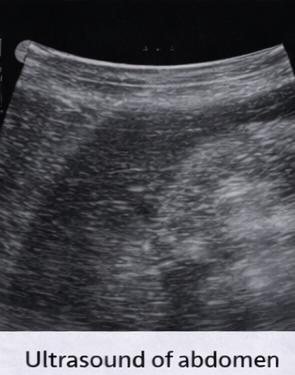

Ultrasound of the abdomen revealed mild hepatosplenomegaly without focal lesions.